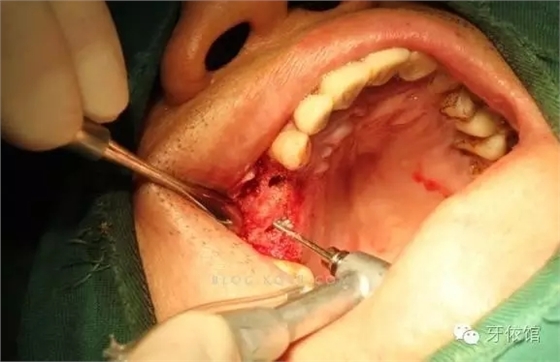

切開翻瓣

640.webp (1).jpg

右上4,6牙位定位,先鋒鉆鉆至距離上頜竇底1-2mm處,改用CAS鉆穿透一個(gè)窩洞竇底。